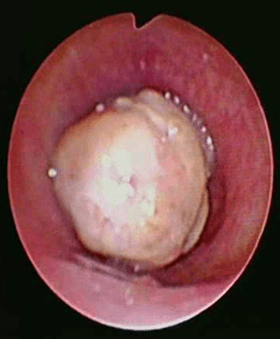

Contrast enhanced computed tomography (CECT) of neck and thorax reported intraluminal mildly enhancing polypoidal mass lesion measuring 2.58 x 1.54 x 1.51 cm (Cc X AP X Tr) in the upper trachea at the level of C6, C7 vertebral body. Significant luminal compromise was noted at the level of the mass lesion. Rest of the lung parenchyma was unremarkable. Flexible bronchoscopy examination revealed a large polyploidal growth approximately 3 cm from the vocal cords. The growth was moving with respiration and causing critical airway narrowing at the upper trachea (approximately 80%).

Patient had primary tracheal tumor. The tumorous growth was significantly blocking the upper trachea causing breathing difficulties and demanding immediate tumor resection.

Patient was intubated using a rigid bronchoscope (EFER DUMON, 10.00/9.20 mm tracheal tube) after induction with fentanyl and propofol. The procedure was done under total intravenous anaesthesia. After successful intubation with the rigid bronchoscope, flexible bronchoscope was passed through the rigid scope. A 4mm MLS endotracheal tube with standard cuff was passed next to the rigid bronchoscope and was positioned beyond the tumour with cuff inflated at about 4 cm above the carina. This approach helps the endoscopist to have total control of the ventilation through out the procedure. Initial attempt was made to cut the stalk of the tumour using an electrosurgical snare, but was unsuccessful as the tumour was attached on to the trachea at multiple sites. Tumour destruction was performed using argon plasma coagulation probe. Non-contact APC was used initially to achieve deep coagulation and effective devitalization of the tumour. After effective coagulation, the cryoprobe was pressed in to the tumour and freezing was performed. The tumour was removed with cryo-extraction technique by repeatedly freezing the tumour and extracting it until the complete tumour is removed from the lumen of the trachea. The tumour base is coagulated using APC probe and contact tamponade with the rigid tracheoscope barrel. Patient is extubated immediately after the procedure.